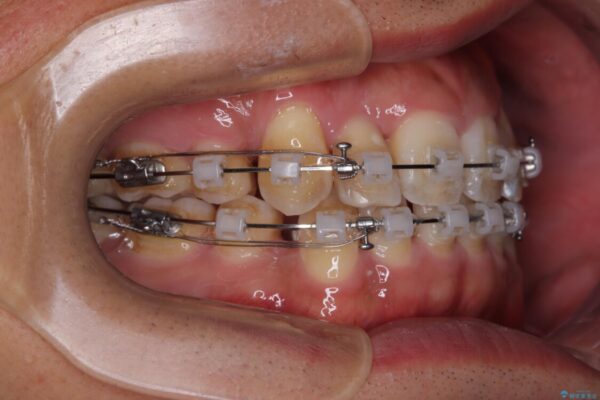

矯正装置は、審美性と費用面のバランスを考慮して、プラスチックブラケットとメタルワイヤーを使用しました。

透明感のあるブラケットを用いたため、従来の金属装置よりも目立ちにくく、日常生活での見た目の不安も軽減できます。

治療途中

• 八重歯と前歯のガタガタを抜歯矯正で治療|クリアブラケット使用例 治療途中画像